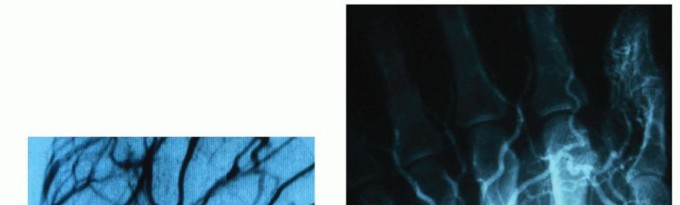

Vascular malformations are uniformly present at birth but may not be visible until childhood, adolescence, or adulthood. Most appear by ages 2 to 5 years.36 They enlarge proportionately with the child unless they are stimulated by trauma, hormones, infection, or surgery.4 These lesions have an equal sex distribution.Malformations generally have flat, slowly dividing endothelial cells.Vascular malformations present with a mass or skin discoloration depending on the depth of the lesion. They enlarge shortly after birth and grow with the child.31It is important to differentiate vascular malformations from hemangiomas because vascular malformations do not involute. Growth is due to progressive dilatation of the vessels and recurrence or regrowth after excision isdue to alteration in hemodynamics and rerouting of flow through previously quiescent aberrant channels (FIG 4).Patients with vascular malformations will complain of the mass effect of the lesion, increased size with exercise, or pain due to thrombosis. Elevation of the extremity eases symptoms. These lesions may lead to nerve compression at the forearm and wrist and digital compression may be seen with localizedthrombosis.31,33Vascular malformations consist of venous, capillary, arterial, and lymphatic malformations. Because up to 70% of vascular malformations are mixed, classification is not always straightforward. In the Hamburg classification, vascular malformations of the extremities are classified by the predominant vascular defect and by whether atruncular or extratruncular form, depending on involvement of a major axial vessel.3Vascular malformations are also classified as either low-flow or high-flow lesions based on their radiographic appearance and clinical characteristics. Before the routine use of magnetic resonance imaging (MRI) and Doppler ultrasound (US), angiography was used to estimate flow rates and shunt volume. Based on these findings, high-flow lesions were distinguished from low-flow lesions by the caliber and rate of opacification of feeding and draining vessels. The use of angiography has been augmented—and increasingly supplanted— by the development of Doppler US, nuclear scanning, and MRI, which have allowed more precisemeasurement of flow velocities, shunt volumes, and soft tissue anatomy.18Low-flow malformations have large channels without intervening parenchyma and often are associated with phleboliths. These lesions are more common than high-flow lesions, representing 90% of vascularmalformations. They consist mainly of venous, capillary, and lymphatic malformations.32High-flow malformations usually have an arterial component and arteriovenous shunting. Marked enlargement and increased number of arteries, small vessels, and veins are consistent findings.5High-flow malformations present early as a painless mass. They have a bimodal occurrence: 40% show upat birth and another 34% after 10 years old.31 They do not contract with elevation. Later in childhood, they can become painful and lead to distal ischemia or even high-output heart failure if large and untreated.They have been divided into three types:Type A lesions have single or multiple AVFs, aneurysms, or ectasias involving the arterial side. They are localized to a specific anatomic region.32,36Type B lesions consist of arteriovenous anomalies with microfistulas or macrofistulas that are localized to a single limb, hand, or digit. They have stable flow characteristics and provoke minimal to no distal symptoms. As with type A lesions, they remain localized to an anatomic region.32,36Type C lesions enlarge slowly. They are diffuse, with microfistulas and macrofistulas involving all limb tissues. With increasing size, vascular steal occurs. They can cause distal ischemic pain, tachycardia, and congestive heart failure. Compartment syndrome, compression neuropathies, and ulceration secondary to ischemia or attempted surgical interventions can occur. The result can be unrelenting,progressive pain, eventually leading to amputation.31,32 These lesions are notoriously difficult to treat.32

Plain radiographs of the digits and handsPhleboliths (in 6%) and bony hypertrophy may be noted.20,24There may be evidence of a soft tissue mass or signs of bone erosion or destruction of the cortical surface, which is seen in about 6% of patients with hemangiomas.24Doppler ultrasonic flow detection is a noninvasive study that does not require the use of contrast.It has been used to confirm high-flow anomalies and to help differentiate between hemangiomas and malformations.31 Doppler ultrasonography will show these lesions to be monophasic with low-flow velocity averaging 0.22 kHz.30Computed tomography with contrast enhancement may show bony involvement of the tumor, especially in type A high-flow malformations.32MRI/magnetic resonance angiography (MRA) can be used to evaluate the site, size, flow rate, and characteristics of the lesion as well as involvement of contiguous structures.32It may be used to determine whether a malformation is low flow or high flow and can also distinguish between dense parenchymal lesions and malformations with large vascular channels.14It can also be used to evaluate glomus tumors, which have a high signal intensity on T2-weighted spin-echo MRI or after gadolinium injection.21MRI has a sensitivity of 90% and a specificity of 50% for glomus tumors, so that it cannot be used as the only diagnostic study for glomus tumors, especially if they are less than 2 to 3 mm in size.2Hemangiomas will appear as well-circumscribed mass lesions that enhance with gadolinium and will have a high T1 signal secondary to infiltrative margins and fatty tissue overgrowth as well an extremely high,heterogeneous T2 signal. A serpentine pattern in the mass may also be seen on MRI.36MRA may be performed at the time of MRI to evaluate lesions in patients who are unable to undergo angiography secondary to renal problems or contrast allergies. It can be used to define the anatomic extent of lesions and their relationship with the surrounding tissue. It can be used to evaluate for both arterial andvenous tumors without contrast enhancement.8Technetium 99m red blood cell perfusion and blood pool scintigraphy will show increased activity on early and late blood pool images with increased perfusion in hemangiomas and may be useful in their diagnosis.36 Angiography is the gold standard evaluation of certain tumors, including vascular malformations. No longerroutinely used for diagnosis of a lesion, it is used as an evaluation for operation or embolization.32 It may showa cluster of anomalous arterial branches with multiple communications with venous trunks draining the site of involvement.22Closed venous angiography uses contrast injected into the venous system distal to a proximal arterial tourniquet applied on the upper arm. Contrast is injected into the exsanguinated extremity distal to the tumor,and radiographs are taken as the vascular tumor fills to get an accurate assessment of the anatomy.20 Arterial angiography is performed through a stick into the femoral artery with a catheter that is fed into the involved extremity. Dye is then injected and both the arterial and venous phases of circulation are evaluated. This can be used to evaluate the size of the tumor, locate the feeding vessels, and embolize feeding vessels beforeoperation (FIG 12).20